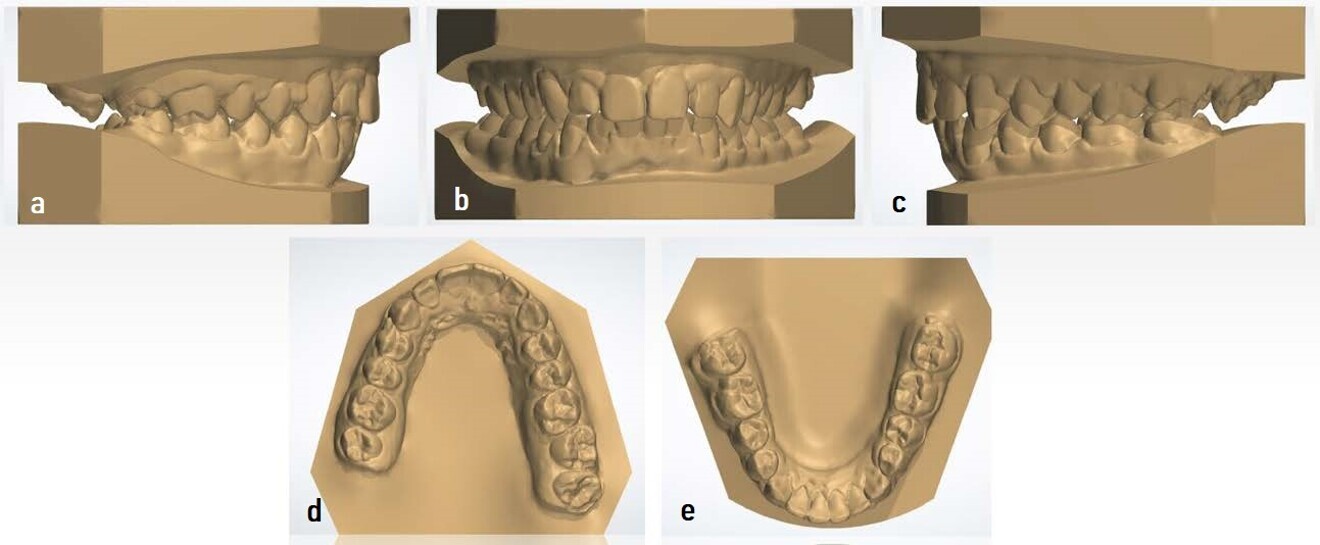

In the model analysis, the same results as seen in the intra-oral analysis were observed. The dental models were scanned with iTero (Align Technology) for their subsequent digitisation and study (Fig. 8). This facilitated the data collection and interpretation, as well as the confirmation of an 11 mm overjet. The models were measured with 3Shape Dental System. Records were taken for subsequent comparison with the final models after the treatment.

Figs. 8a–e: Initial digital models showing a bilateral Class II malocclusion and an overjet of 11 mm (images generated using 3Shape Dental System).